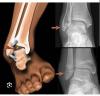

Девочки , кто подскажет ушиб это?? Сын не удачно приземлился на батуте днем и не может на ногу наступать до сих пор(

@tankanv31, она еще больше опухла( съездили мы, вообще наступать не может на нее( перелома нет, слава богу. Растяжение , мазать будем , сказали поболит и перестанет..

Немного посинело да(( но я даже когда просто дотрагиваюсь , ему больно

Похоже на вывих